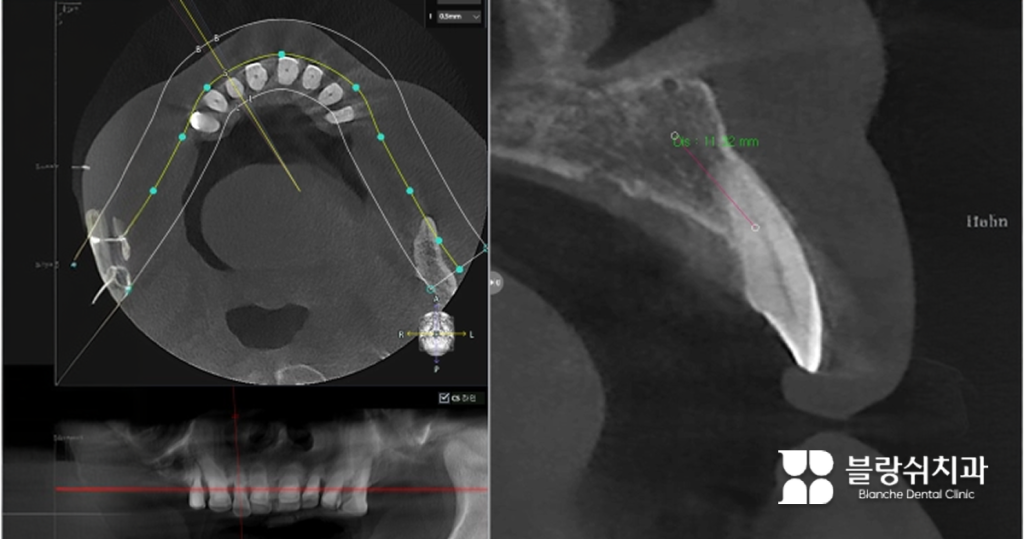

- 상황 기존 보철 치료 이력이 있는 성인 남성 환자분으로, 아래 어금니 부위에 치아가 상실된 상태였습니다. 특히 하악의 경우 신경관이 가까이 지나가기 때문에 깊이 조절이 중요했습니다.

- 치료방법 잇몸뼈 상태를 확인하고, 무절개로 진행했습니다. 특수장비로 뚫은 작은 구멍을 통해 임플란트를 식립했습니다.

비절개가 더 쉬울까요? 그렇지 않습니다. 오히려 더 철저하게 준비해야 해요. 잇몸을 열지 않는다는 건 뼈의 두께, 밀도, 신경 위치까지 정확하게 파악해야 한다는 의미이기도 합니다. 블랑쉬 치과가 대학병원급 디지털 장비를 갖춘 이유가 여기에 있습니다. 저희는 단 0.1mm 오차도 허용하지 않으려 합니다.